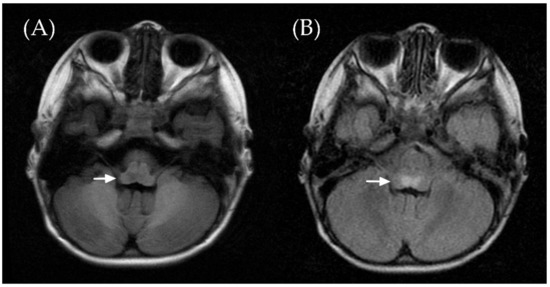

2. Case Report